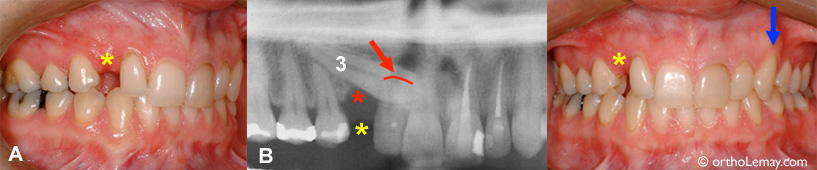

Femme de 26 ans avec une bonne occlusion, sauf pour une canine incluse qui a causé des dommages à l’os et à une dent adjacente. Voir les explications ci-dessous. (Femme – 26 ans)

Cet autre exemple pourrait démontrer ce qui peut arriver au cas précédent s’il était laissé sans supervision pendant plusieurs années.

• (A) Une femme de 26 ans a une condition similaire au cas 1 ci-haut; elle présente une canine supérieure droite complètement formée, mais sévèrement incluse du côté du palais (B-3).

• Cette condition, qui est en progression depuis au moins 15 ans, aurait possiblement pu être évitée avec une supervision adéquate pendant l’éruption des dents (prise de radiographies et extractions sélectives).

• Le fait d’avoir gardé la canine incluse pendant toutes ces années a eu plusieurs conséquences dommageables pour l’environnement de cette dent :

• Avec les années, la canine temporaire est tombée lorsque la canine permanente incluse a progressivement usé sa racine. Il en résulte un espace important et inesthétique où était la canine temporaire (* jaune).

• (B) La canine incluse a résorbé (usé) plus de 40% de la racine de l’incisive permanente latérale supérieure droite. La flèche et la ligne rouges indiquent le bout de la racine usée. La santé et survie de cette incisive latérale sont maintenant incertaines à long terme.

• Un défaut osseux très important (perte d’os visible en foncé sur la radiographie) s’est développé dans la région de la canine droite (* rouge) de sorte qu’une tentative de loger la canine dans l’arcade peut nécessiter une chirurgie pour ajouter de l’os ou être vouée à l’échec.

• En comparaison, la canine gauche est descendue normalement par elle-même (flèche bleue).